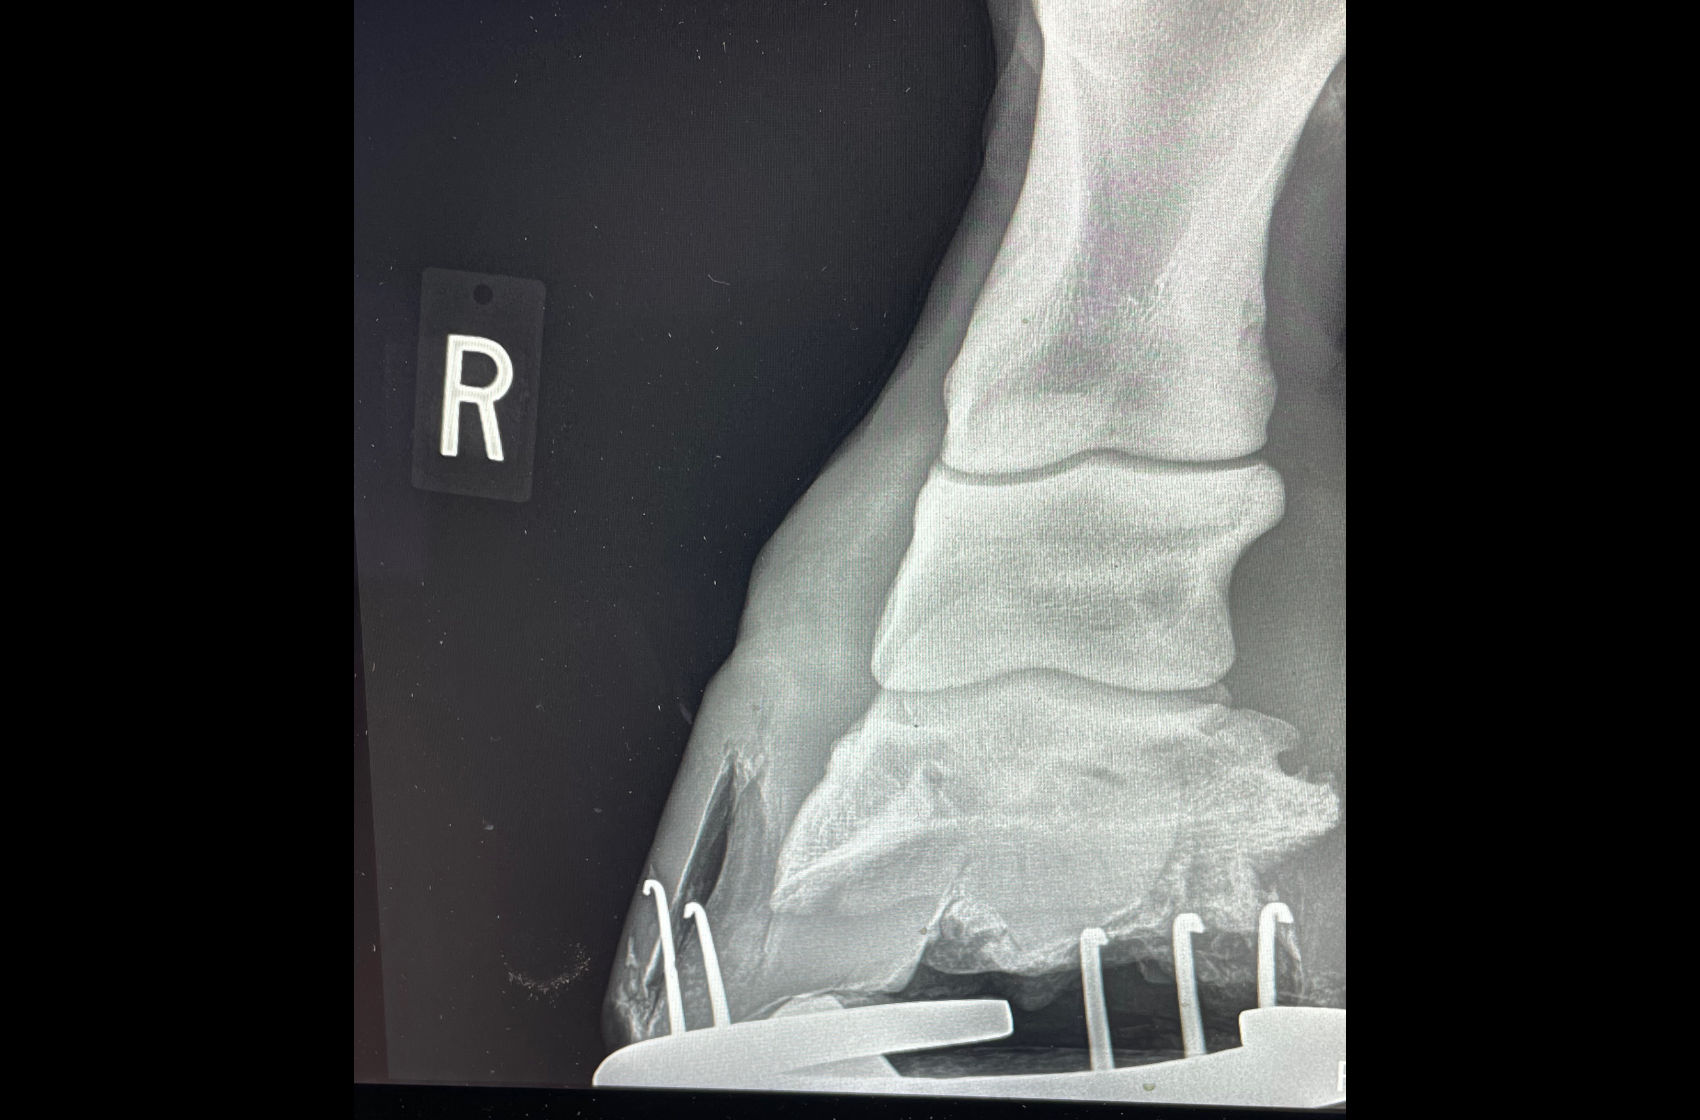

Horse landed badly from jump and became acutely lame.